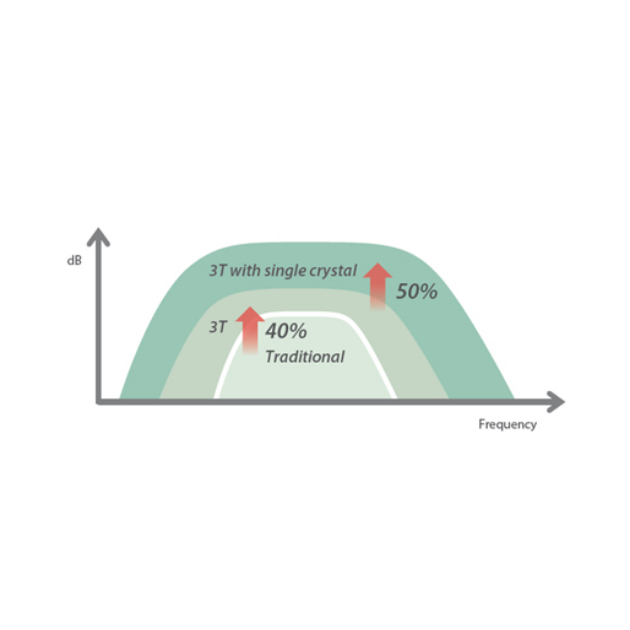

eXpress Clarity

More clarity at handUltra-light volume transducer with superior performance

The ultra-light and high-density volume transducer D8-2E offers superior obstetric imaging performance across 2D, Color and 3D/4D for more diagnostic confidence and patient care.